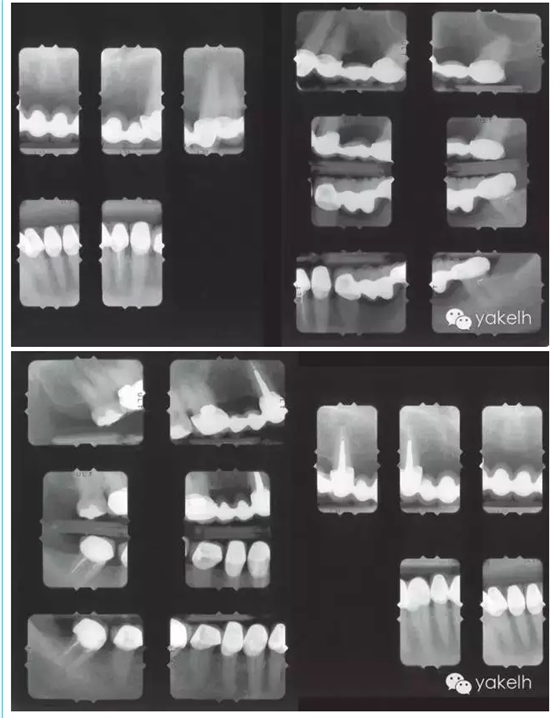

上頜天然牙牙支持式固定橋更換為種植體支持式固定橋,其他用單冠及牙支持式固定橋修復(fù)(病例)

¤¤因關(guān)鍵基牙遠(yuǎn)期預(yù)后較差,臨床上經(jīng)常需要將牙支持式固定橋換成種植體支持式固定橋。治療的困難在于整個治療過程中因為患者不能接受活動的暫時修復(fù)體,需要制作固定的暫時修復(fù)體。該患者在其他國家進(jìn)行了整個牙合重建。但對結(jié)果不滿意,也不喜歡美學(xué)效果,上唇過于凹陷,咬合也不舒適。此外,修復(fù)體結(jié)構(gòu)和邊緣適合也不足,需要全部更換。部分牙齒缺失,并且關(guān)鍵基牙—右上尖牙,遠(yuǎn)期預(yù)后差。因此,治療計劃包括植骨在內(nèi)的口腔種植手術(shù)。